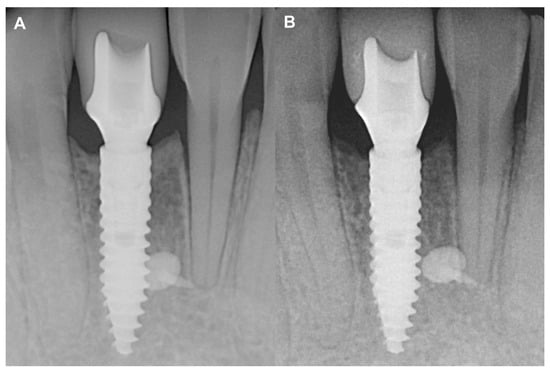

3.1.2. Short-Term Hard Tissue Gain and Two-Year Follow-Up

3.2.2. Short-Term Volumetric Hard Tissue Gain and Long-Term Follow-Up